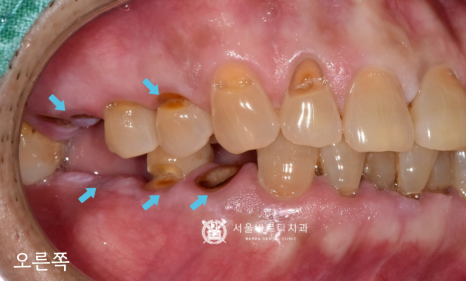

정면 사진을 보시면

목 부위가 V자로 깨져나간 것이 확인되네요.

큰 어금니가 없는 기간 동안

작은 어금니와 앞니에 무리한 힘이 가해져서

깨진 것도 있겠지만

50대의 비교적 젊은 남성분이라서

식사하는 힘이 강하신 것을 알 수 있는데요.

아마 틀니로 넣어드리게 된다면

식사하는 힘을 견디기 어렵고,

틀니가 깨지거나 잇몸에 상처가 나서

사용이 불편하셨을 것입니다.